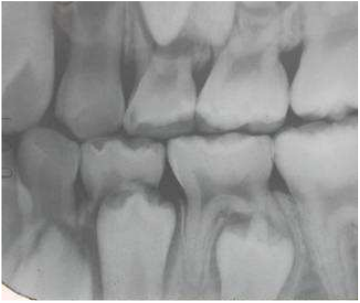

37.如下X光圖所示,關於左下第二小臼齒,你的診斷為何?

(A)牙釉珠(enamel pearl) (B)齒外齒(dens evaginatus) (C)齒中齒(dens invaginatus) (D)黏合齒(gemination)